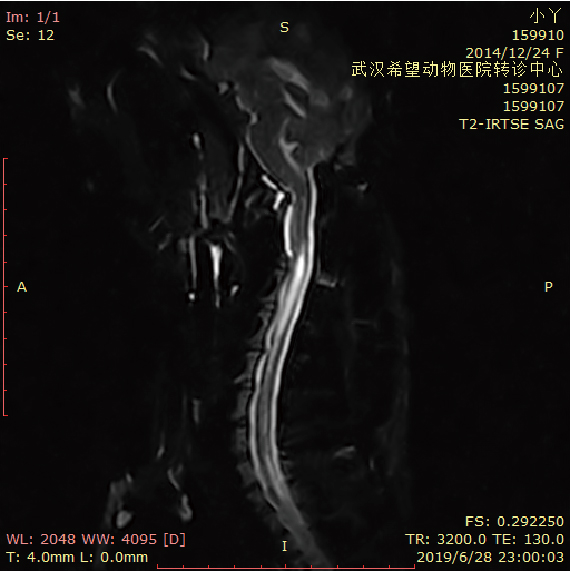

MRI’s applications in the musculoskeletal system include spinal imaging, assessment of joint disease, and soft tissue tumors. Hepatobiliary MRI is used to detect and characterize lesions of the liver, pancreas, and bile ducts. MRI is also used to evaluate the arteries of the neck and brain, the thoracic and abdominal aorta, the renal arteries, and the legs.

Canine Spine